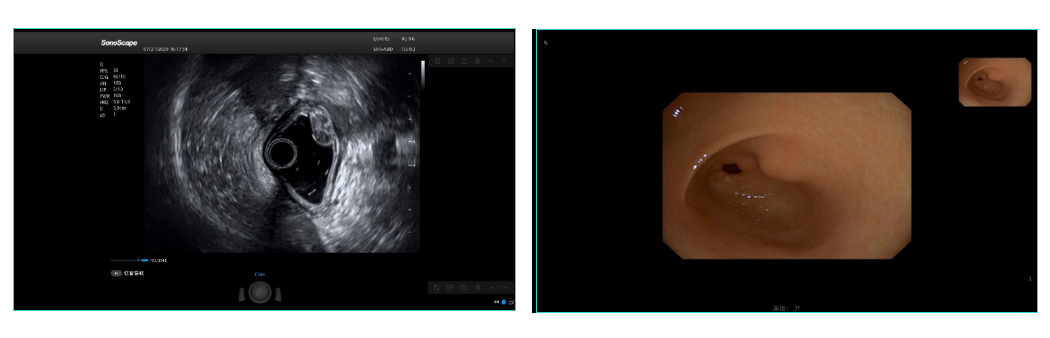

据悉,EG-UR5的微小光学成像模组、高密度超声探头等核心部组件均为自主研发,可同时提供高清晰度的光学图像和具有高分辨率的超声图像,并支持辅助医生诊断的多种成像模式。

在超声系统层面,环阵超声内镜EG-UR5搭配了开立医疗最高端的超声主机S60,可以适配多种应用探头,满足超声、内镜与临床全科室应用,节约医院成本;而140°的视野角和0度的视野方向,则使进境更容易;头端部外径11.3mm,更细的外径保证医生操作的同时降低患者的不适感;强大的超声系统带来4.5-12MHz超宽频带成像,探测深度可达80mm,兼顾成像优异的同时能更好地满足临床医生的诊疗需要;由于开立医疗超声内镜的先端硬质段更短,具有良好的操控性,能有效降低手术风险。

超声内镜可以在距病灶最近的位置对病灶进行超声扫描,排除了体表超声检查可能遇到的种种干扰,并采用较高频率的探头,不仅可清晰显示消化道官腔的黏膜病变,还可观察消化道壁及各层组织结构的变化及消化道周围器官的病变。环阵超声内镜EG-UR5无论近场粘膜组织还是中远场周边器官和病变,超声图像都非常清晰,彩色多普勒敏感性和造影成像效果达到了业界最佳水平。比起传统外科的微创方法,超声内镜带来的体内创伤相对较小,综合提升了患者就医质量与服务。

环阵超声内镜具有360°影像,使操作更简便,同时显示消化道管壁一周,可以缩短检查时间,减少遗漏,并提供多种扫描频率,便于清晰显示消化道壁各层组织结构的变化以及周围组织器官的病变,由此医生可以一目了然看清患者体内的情况。